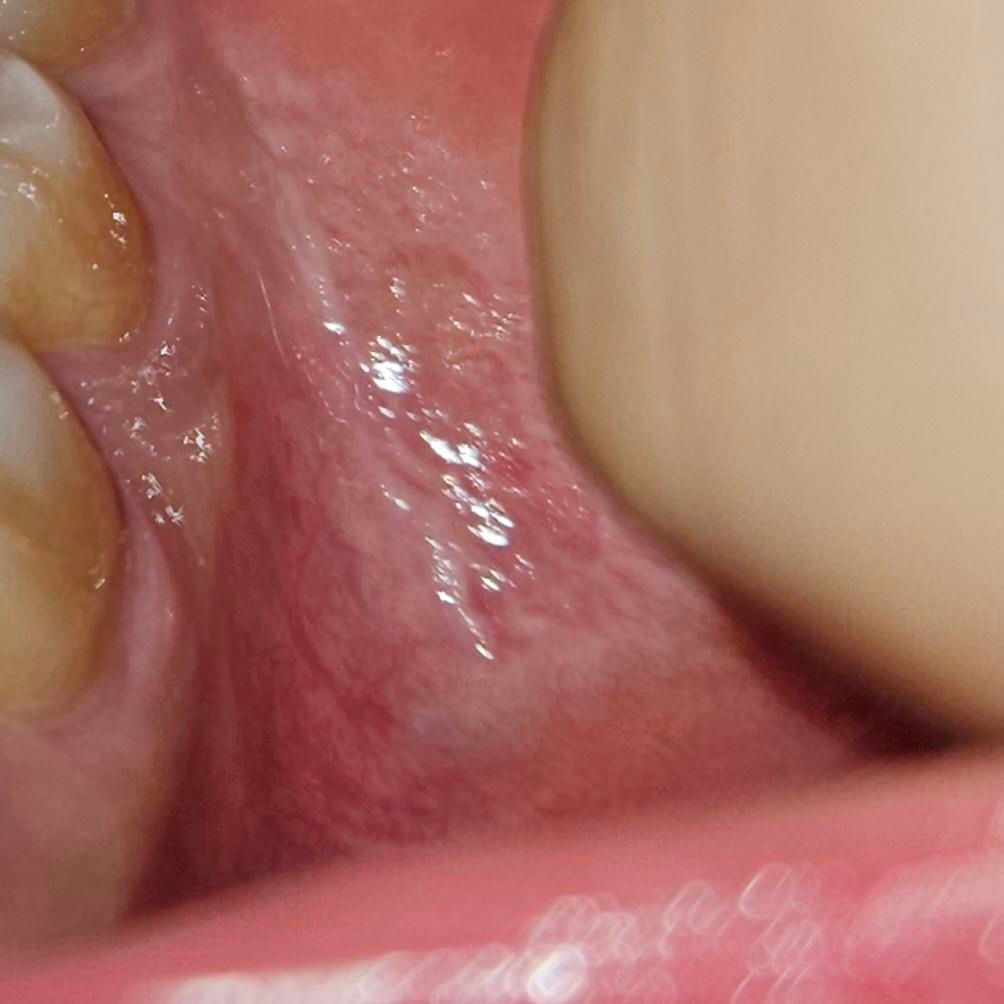

구강 점막 변형 구내염인가요 구강암인가요

통증은 없구요 다민 혀를 갖다데면 거칠거칠합니다

걱정이 되는데 전암병소인가요?

사진으로만 봤을 경우에는 정상 조직과 크게 다른 것이 보이진 않습니다 느낌이 이상하거나 감각이 다르다면 병소가 있을 수 있으니 치과에서 진료를 받아 보는 것이 좋습니다

전암병소의 구별은 조직검사를 받아보셔야하며 대학병원 구강내과로의 내원을 권합니다.

큰 문제가 잇는건 아니고 볼살이 치아에 씹혀서 생긴현상입니다. 너무 걱정은 안하셔도 될것같습니다.

사진상 구내염으로 의심이되며, 크게 문제가 되어 보이지 않습니다. 1-2주 지나면 저절로 낫으며 특별히 빨리 낫게 하는 법은 아직 없습니다.

헥사메딘이라는 소독약으로 입안을 헹구어 주는 것도 도움이 될 수 있습니다.

만약 통증 및 붓기가 지속시에는 치과 진료를 받아보길 권합니다.